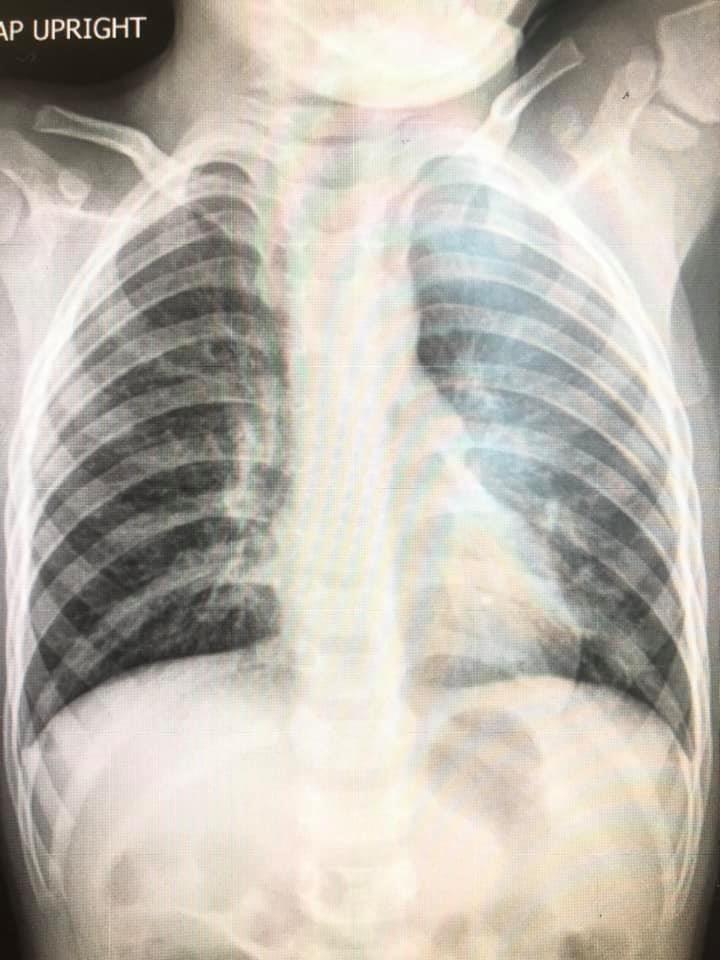

ล่าสุด วันที่ 6 พฤศจิกายน 2563 เฟซบุ๊ก Infectious ง่ายนิดเดียว ได้โพสต์ภาพฟิล์มเอกซเรย์ปอดเด็กที่ติดเชื้อไวรัส RSV 10 คน ที่เข้ารับการรักษาที่โรงพยาบาล โดยได้รับการวินิจฉัยว่ามีอาการหลอดลมอักเสบ ปอดอักเสบ โดยฝ้าสีขาวคือตำแหน่งทีติดเชื้อ สีดำคือปอดปกติ พร้อมระบุข้อเท็จจริงของ RSV ดังนี้